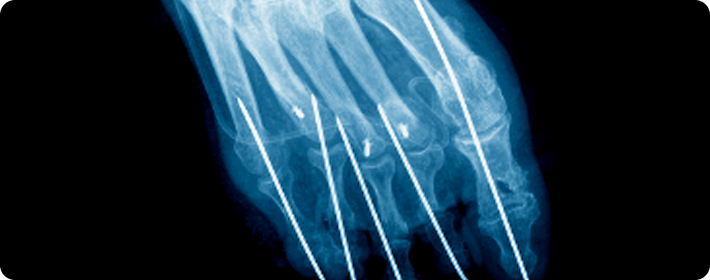

골절고정술

부러진 뼈를 정확한 위치에 맞춘 뒤, 금속판, 나사, 핀 봉 등을 이용해 단단히 고정하여 뼈가 바르게 치유되도록 돕는 수술입니다. 뼈의 정렬을 유지하고 회복을 촉진하는 데 중요한 치료입니다.